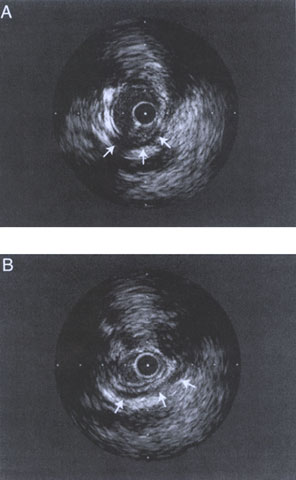

Figure 212-10

Intravascular ultrasound imaging of the myocardial bridging in diastole (A) and in systole (B). A typical half-moon-shaped echolucent area surrounds the bridge during the entire cardiac cycle (arrows). Note the catheter artifact in diastole (A) at seven o'clock.